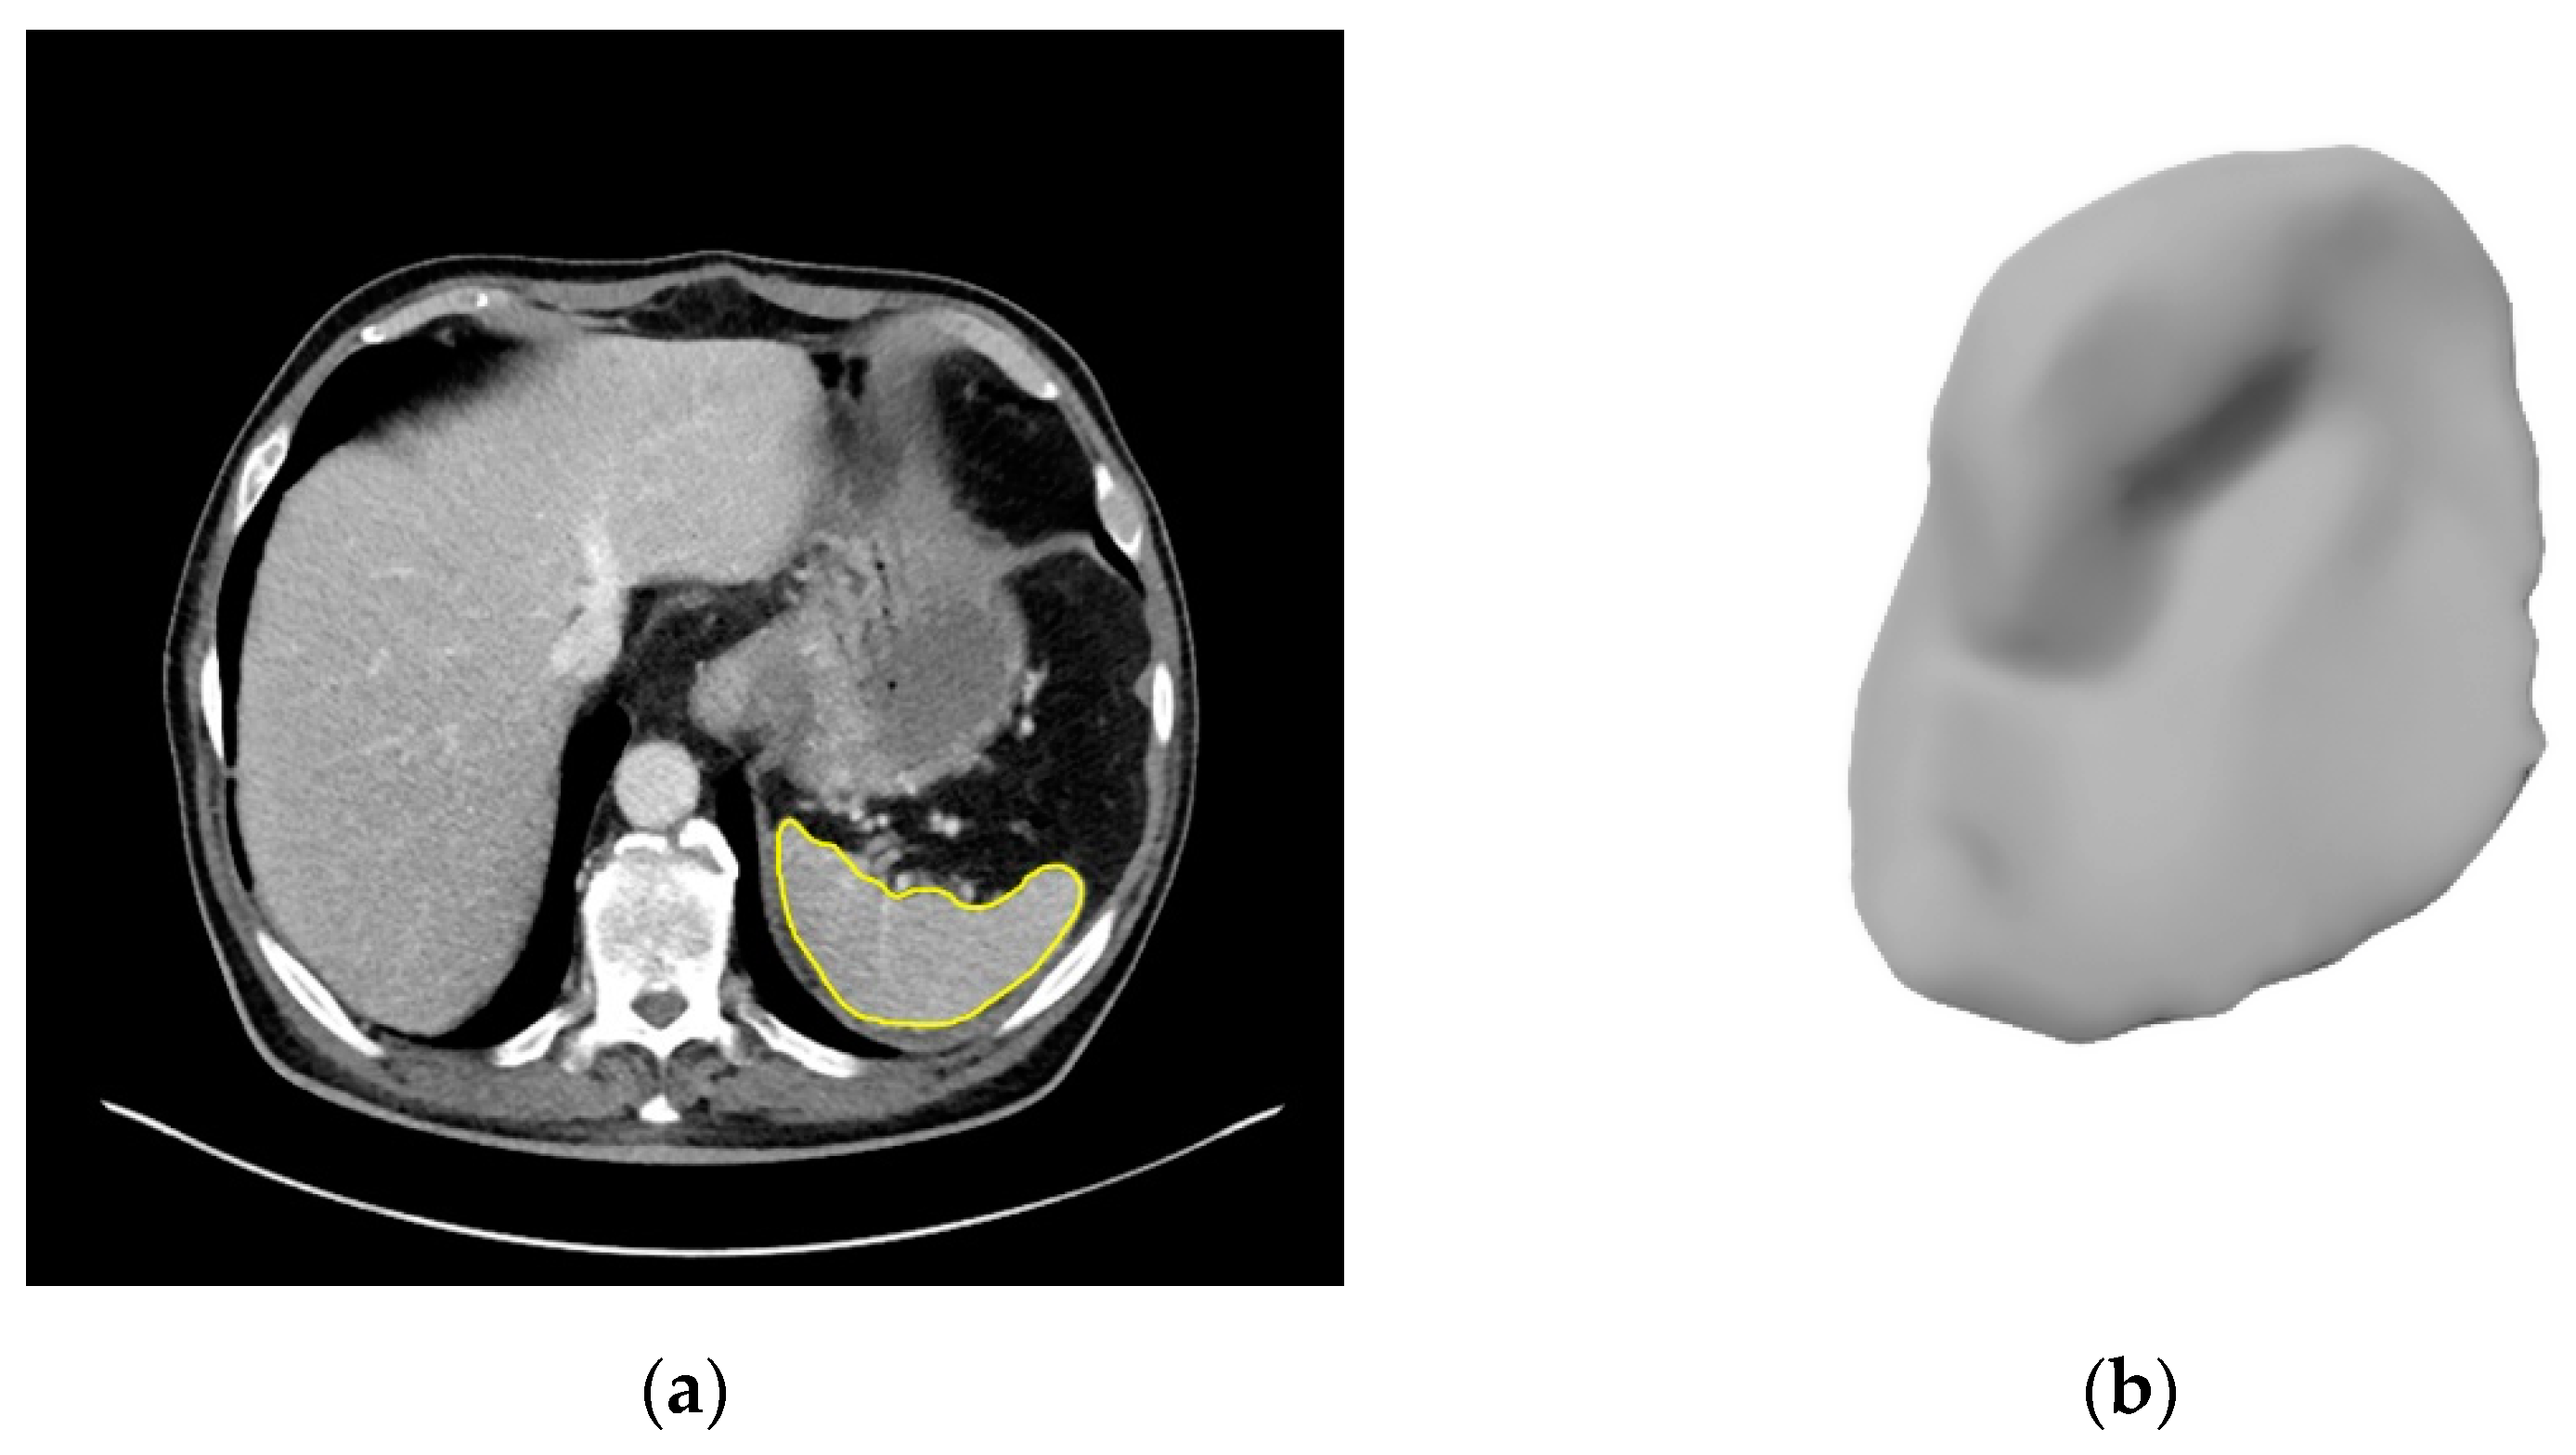

2.3. Image Segmentation

3.2. Segmentations of the Spleen